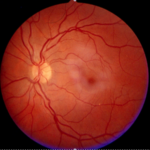

Fond d’oeil sain : la couleur est unie et il n’y a pas de cicatrices